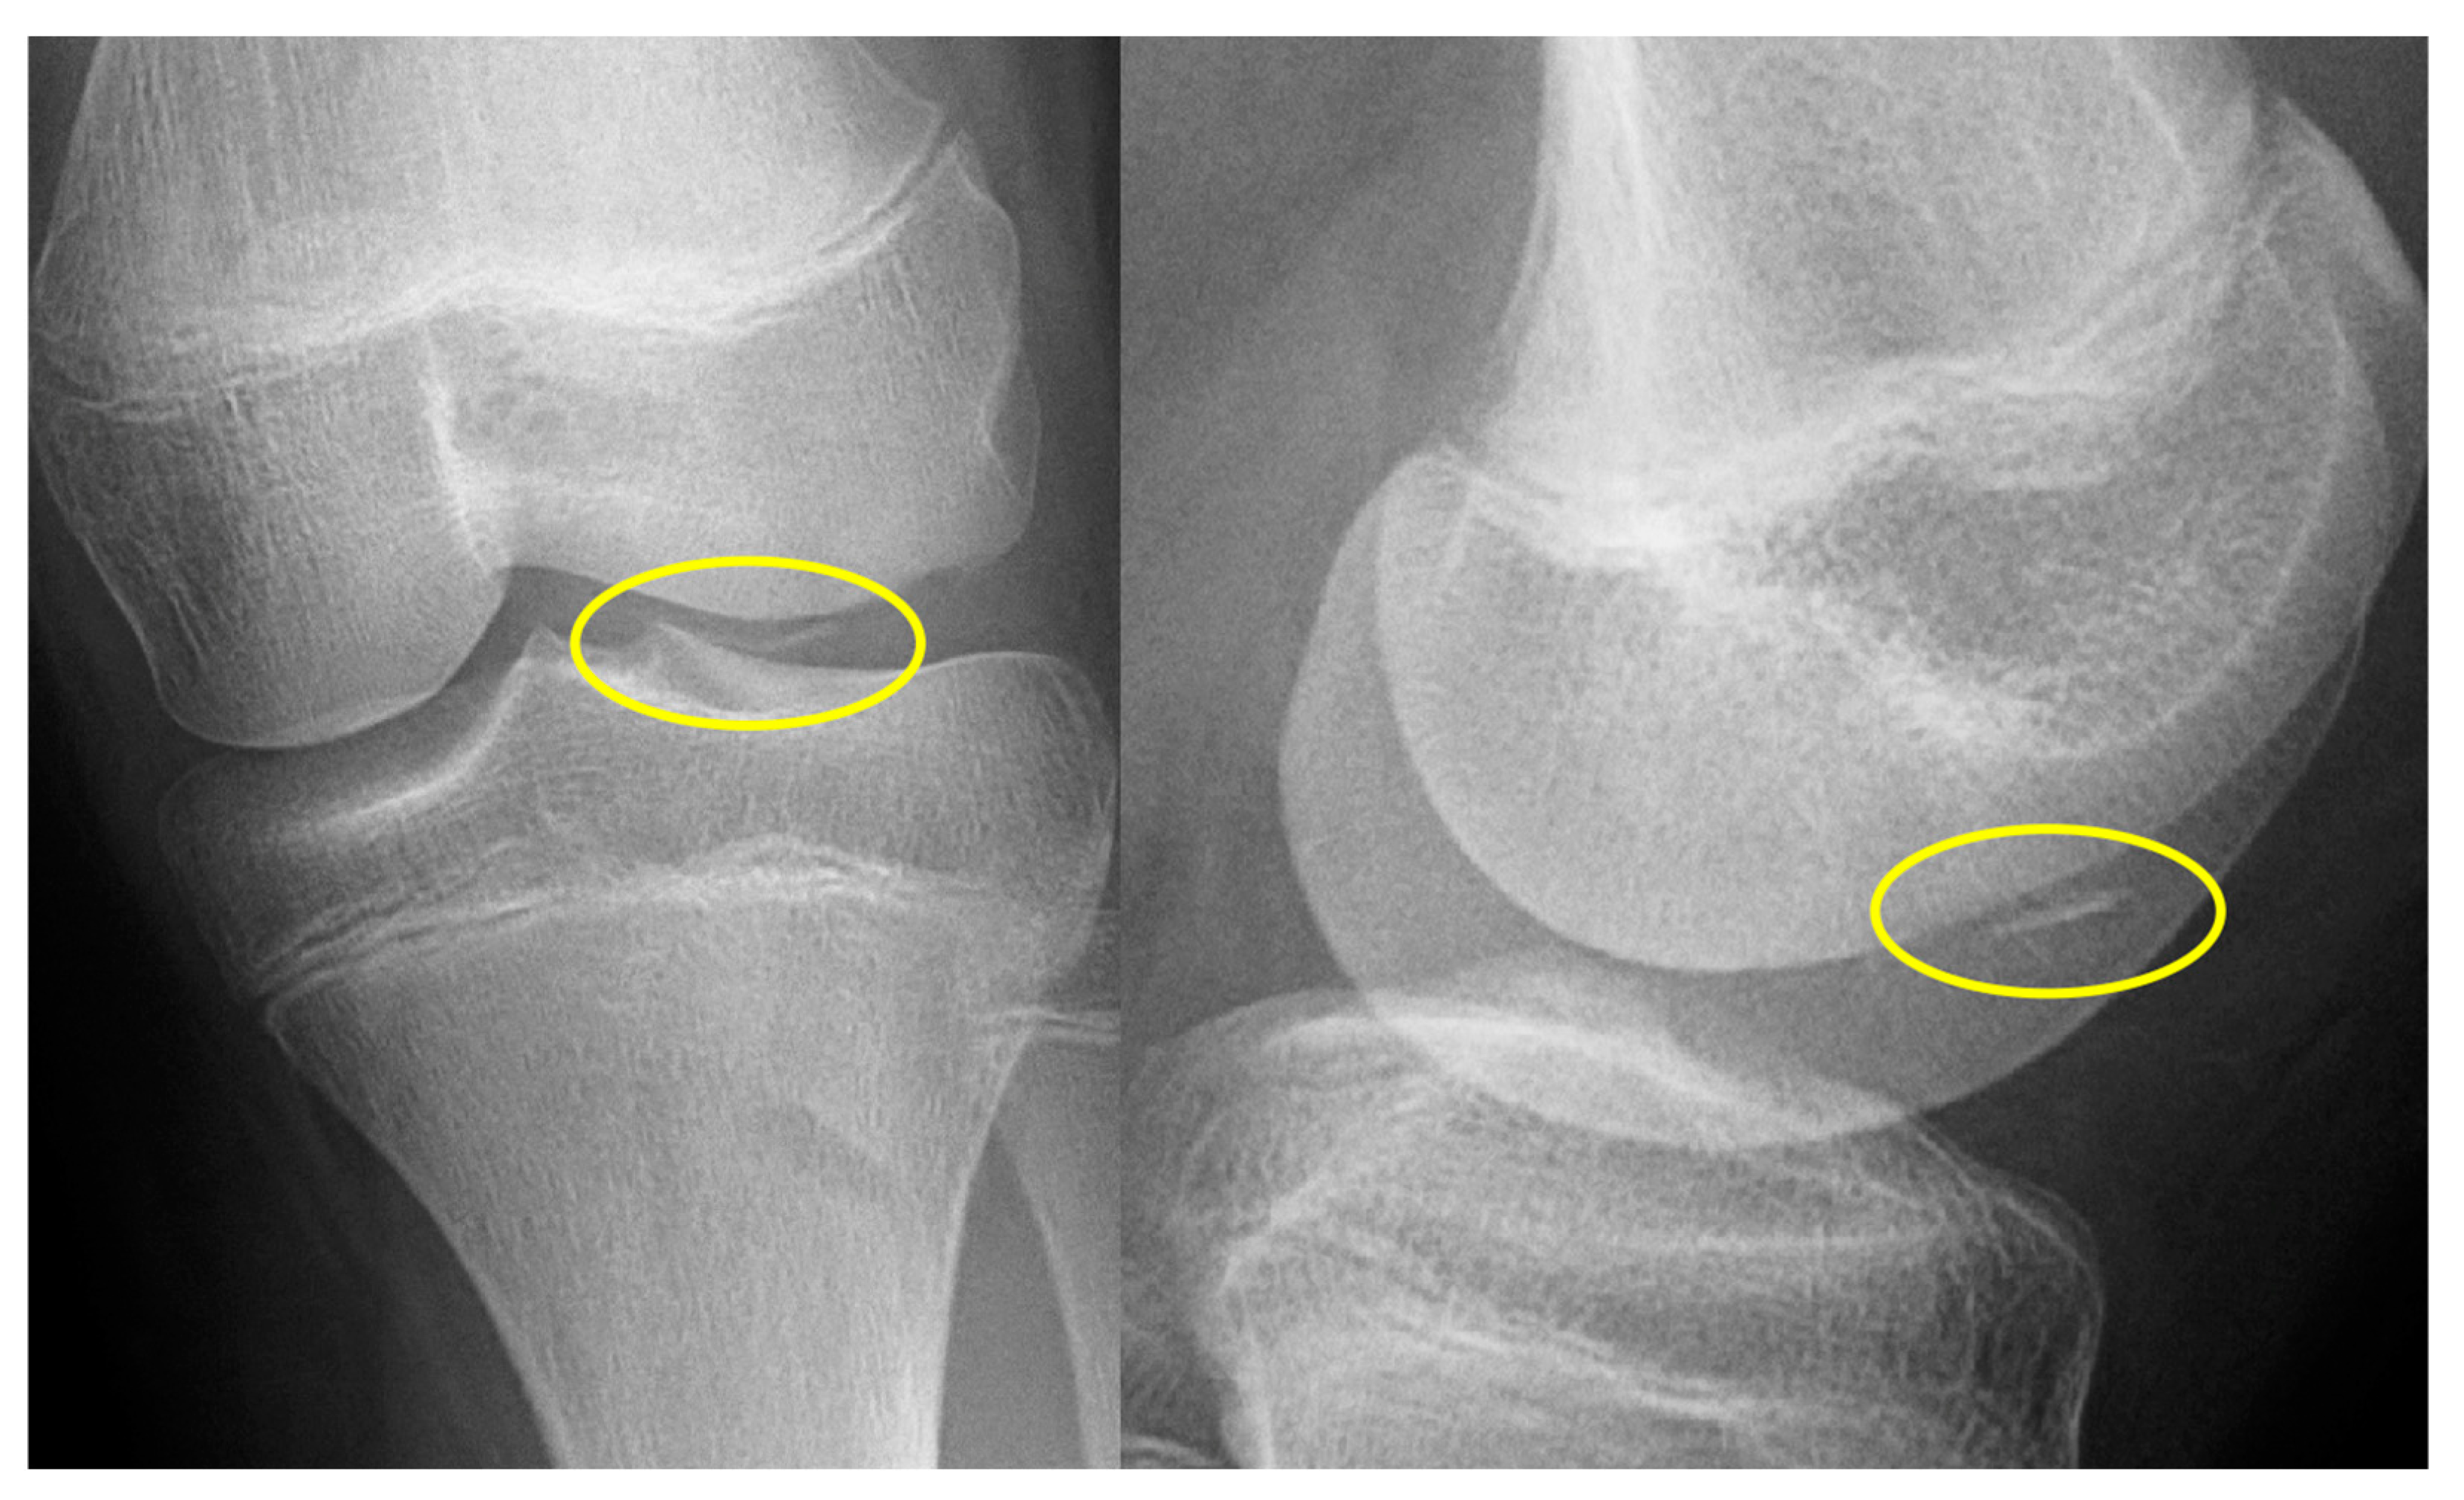

- X-ray: Lucency between fragment and normal bone.

- X-ray: Loose body, lucency